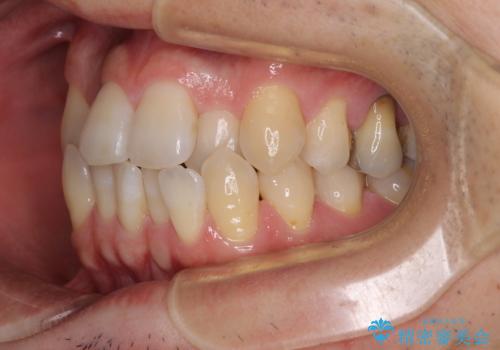

前歯のクロスバイト 目立たないワイヤー装置で矯正治療

- 前歯のクロスバイトを改善したいとのことで来院された患者様です。

マウスピース矯正では前歯の神経への負担が大きいことを懸念され、ワイヤー装置による矯正治療を行うこととしました。

舌の突出癖が認められたため、デコボコ改善に伴い前歯が前突する可能性があったため、舌のトレーニングをしっかりと行うよう指導しながら治療を進めることとしました。